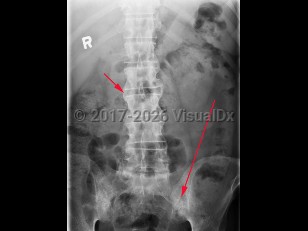

Ankylosing spondylitis is an autoimmune inflammatory disorder characterized by inflammation of the axial skeleton and peripheral joints. It typically begins in the second or third decade of life with a male-to-female prevalence of 2-3:1. There is a high concordance of ankylosing spondylitis in patients with haplotype human leukocyte antigen B27 (HLA-B27).

Patients most typically present with dull pain in the lower lumbar or gluteal region accompanied by early morning stiffness that improves with activity but not with rest. As the disease progresses, pain becomes persistent and bilateral and may worsen at night. Cervical ("chalk-stick") fractures may occur, especially after trauma. In addition to back pain, enthesitis (tenderness at the tendon or ligamentous insertion site to bone) may be common at the costosternal junction, spinous processes, iliac crests, greater trochanters, ischial tuberosities, tibial tuberosities, and heels. Approximately 30% of patients experience arthritis of peripheral joints other than the hips and shoulders. The most common extraarticular manifestation is acute anterior uveitis in up to 40% of patients. A large percentage of others may have inflammation of the terminal ileum or colon, although the majority of cases are asymptomatic. Only a minority of these patients progress to develop inflammatory bowel disease.

Physical examination findings reveal limited spinal mobility with limitation of anterior and lateral flexion / extension of the lumbar spine. Patients may also have limited chest wall expansion and tenderness at the tendinous insertion sites.